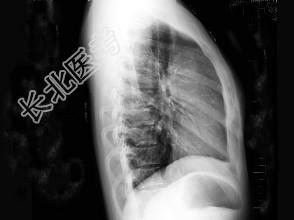

- 单项选择题女,32岁, 感胸闷、胸痛,X线检查如图, 最可能的诊断是 ( )

A、畸胎瘤

B、胸腺瘤

C、淋巴瘤

D、胸骨后甲状腺肿

E、神经源性肿瘤